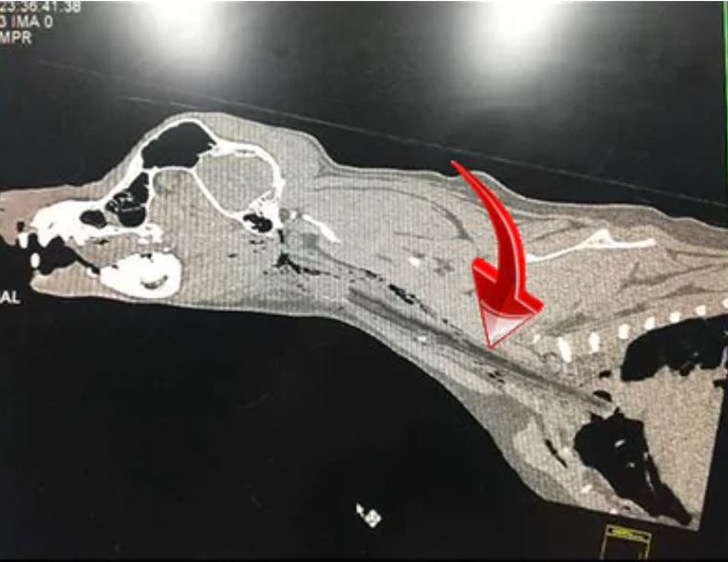

대시가 걱정되었던 가족들은 대시를 동물병원으로 데려갔습니다. 그리고 동물병원에서는 대시가 입 주변가 목 뒤쪽에 통증을 느끼고 있다고 판단했죠. 이후 이들은 엑스레이를 찍어보았는데요. 엑스레이 사진을 본 이후 경악할 수밖에 없었습니다. 바로 흉부 입구로 가는 후두부를 따라 큰 막대기로 추정되는 단단한 이물질을 보았기 때문입니다. 이뿐만이 아니었습니다. 대시의 혀는 관통상을 입었는데요. 곧 이 이물질을 제거하는 수술을 받게 되었습니다.

다행히 대시의 경우 막대기가 가슴 바로 안쪽에 멈춰 심장이나 폐에 구멍을 내지 않았지만 더 심각한 경우에는 이런 막대기로 인해 감염이 일어나 건강과 생명에 큰 영향을 미칠 수 도 있다고 합니다. 그리고 동물 응급실에는 이런 일을 당한 강아지들이 꽤 자주 온다고 하는데요. 절대 막대기를 가지고 놀지 않고 공이나 고무 장난감을 가지고 노는 것이 훨씬 안전하다고 전하고 있습니다.